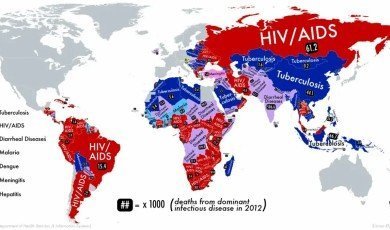

5 of the world’s deadliest infectious diseases

These diseases are caused by pathogenic ...